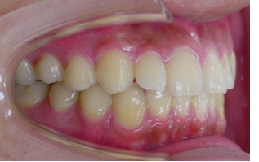

初診時 出っ歯(上顎前突)11歳1カ月 女子

終了時 治療期間2年2カ月 13歳3カ月

見えにくい矯正装置(ブラケット)で歯列を並べていきます。

歯並びが整ったら矯正装置を取り替えます。

MEAW(マルチループ)で咬み合わせの高さを

改善していきます。

13歳2か月 2年2カ月で矯正治療が終了しました。